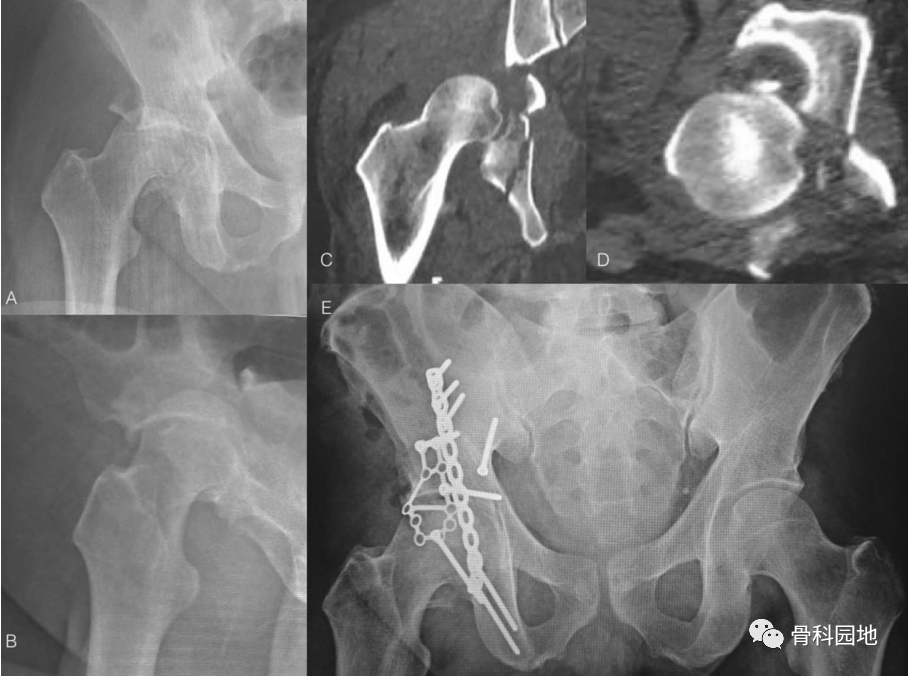

二、髋臼四边体骨折

X线片显示左侧双柱髋臼骨折伴有四边体骨折移位。术后固定情况

三、髋臼后壁粉碎性骨折

使用后柱重建板和用于容纳髋臼粉碎性后壁骨折的跟骨板进行骨折复位和固定